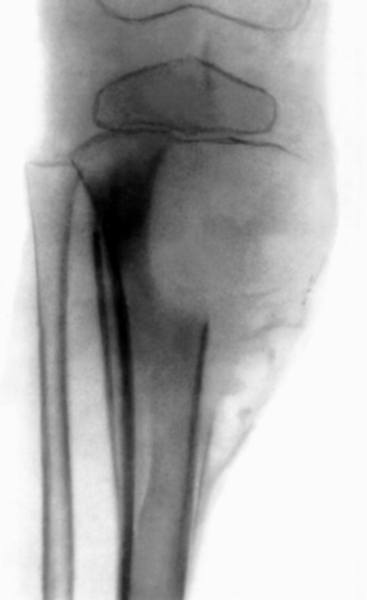

Аневризмальная киста большеберцовой кости (рентгенограмма)